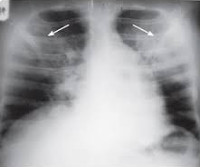

• Рентгенологические исследования. На рентгенограмме грудной клетки определяется изображение отека легких - диффузная инфильтрация легких вплоть до полного затемнения полей легких. Отличительной особенностью этих изменений является их быстрое исчезновение во время лечения.